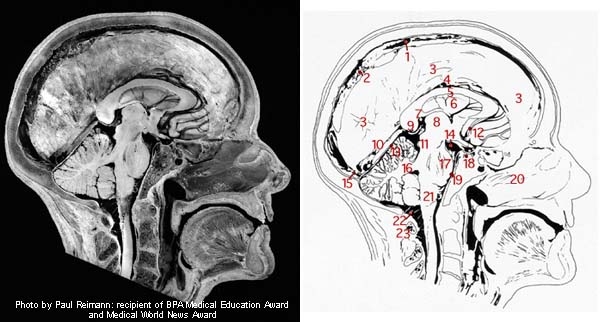

Notations for head drawing below:

1. Superior sagittal sinus 2. Arachnoid granulations 3. Falx cerebri 4. Inferior sagittal sinus 5. Corpus callosum 6. Septum pellucidum 7. Tela choroidea of 3rd ventricle 8. Thalamus 9. Great cerebral vein 10. Straight sinus of tentorium cerebelli 11. Tectum of midbrain 12. Anterior cerebral artery 13. Tentorium cerebelli 14. Interpeduncular cistern 15. Confluence of sinuses 16. Superior cerebellar peduncle 17. Pons 18. Pituitarygland 19. Pontine cistern 20. Nasal septum 21. Medulla oblongata 22. Cerebellomedullary cistern (cisterna magna) 23. Posterior arch of atlas

Remember, the tissues of the body dehydrate and shrink after death to some degree, but these images will give you an idea of what we're dealing with.